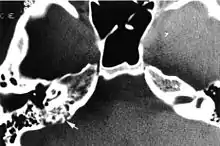

Imaging studies help to identify the tumor and the specific anatomic site of involvement. Magnetic resonance images show a hyperintensity (hypervascularity) of a heterogeneous mass by T1 weighted images. Computed tomography shows a multilocular, lytic destructive temporal bone mass, centered on the vestibular aqueduct (between internal auditory canal and sigmoid sinus).[1][6][7]